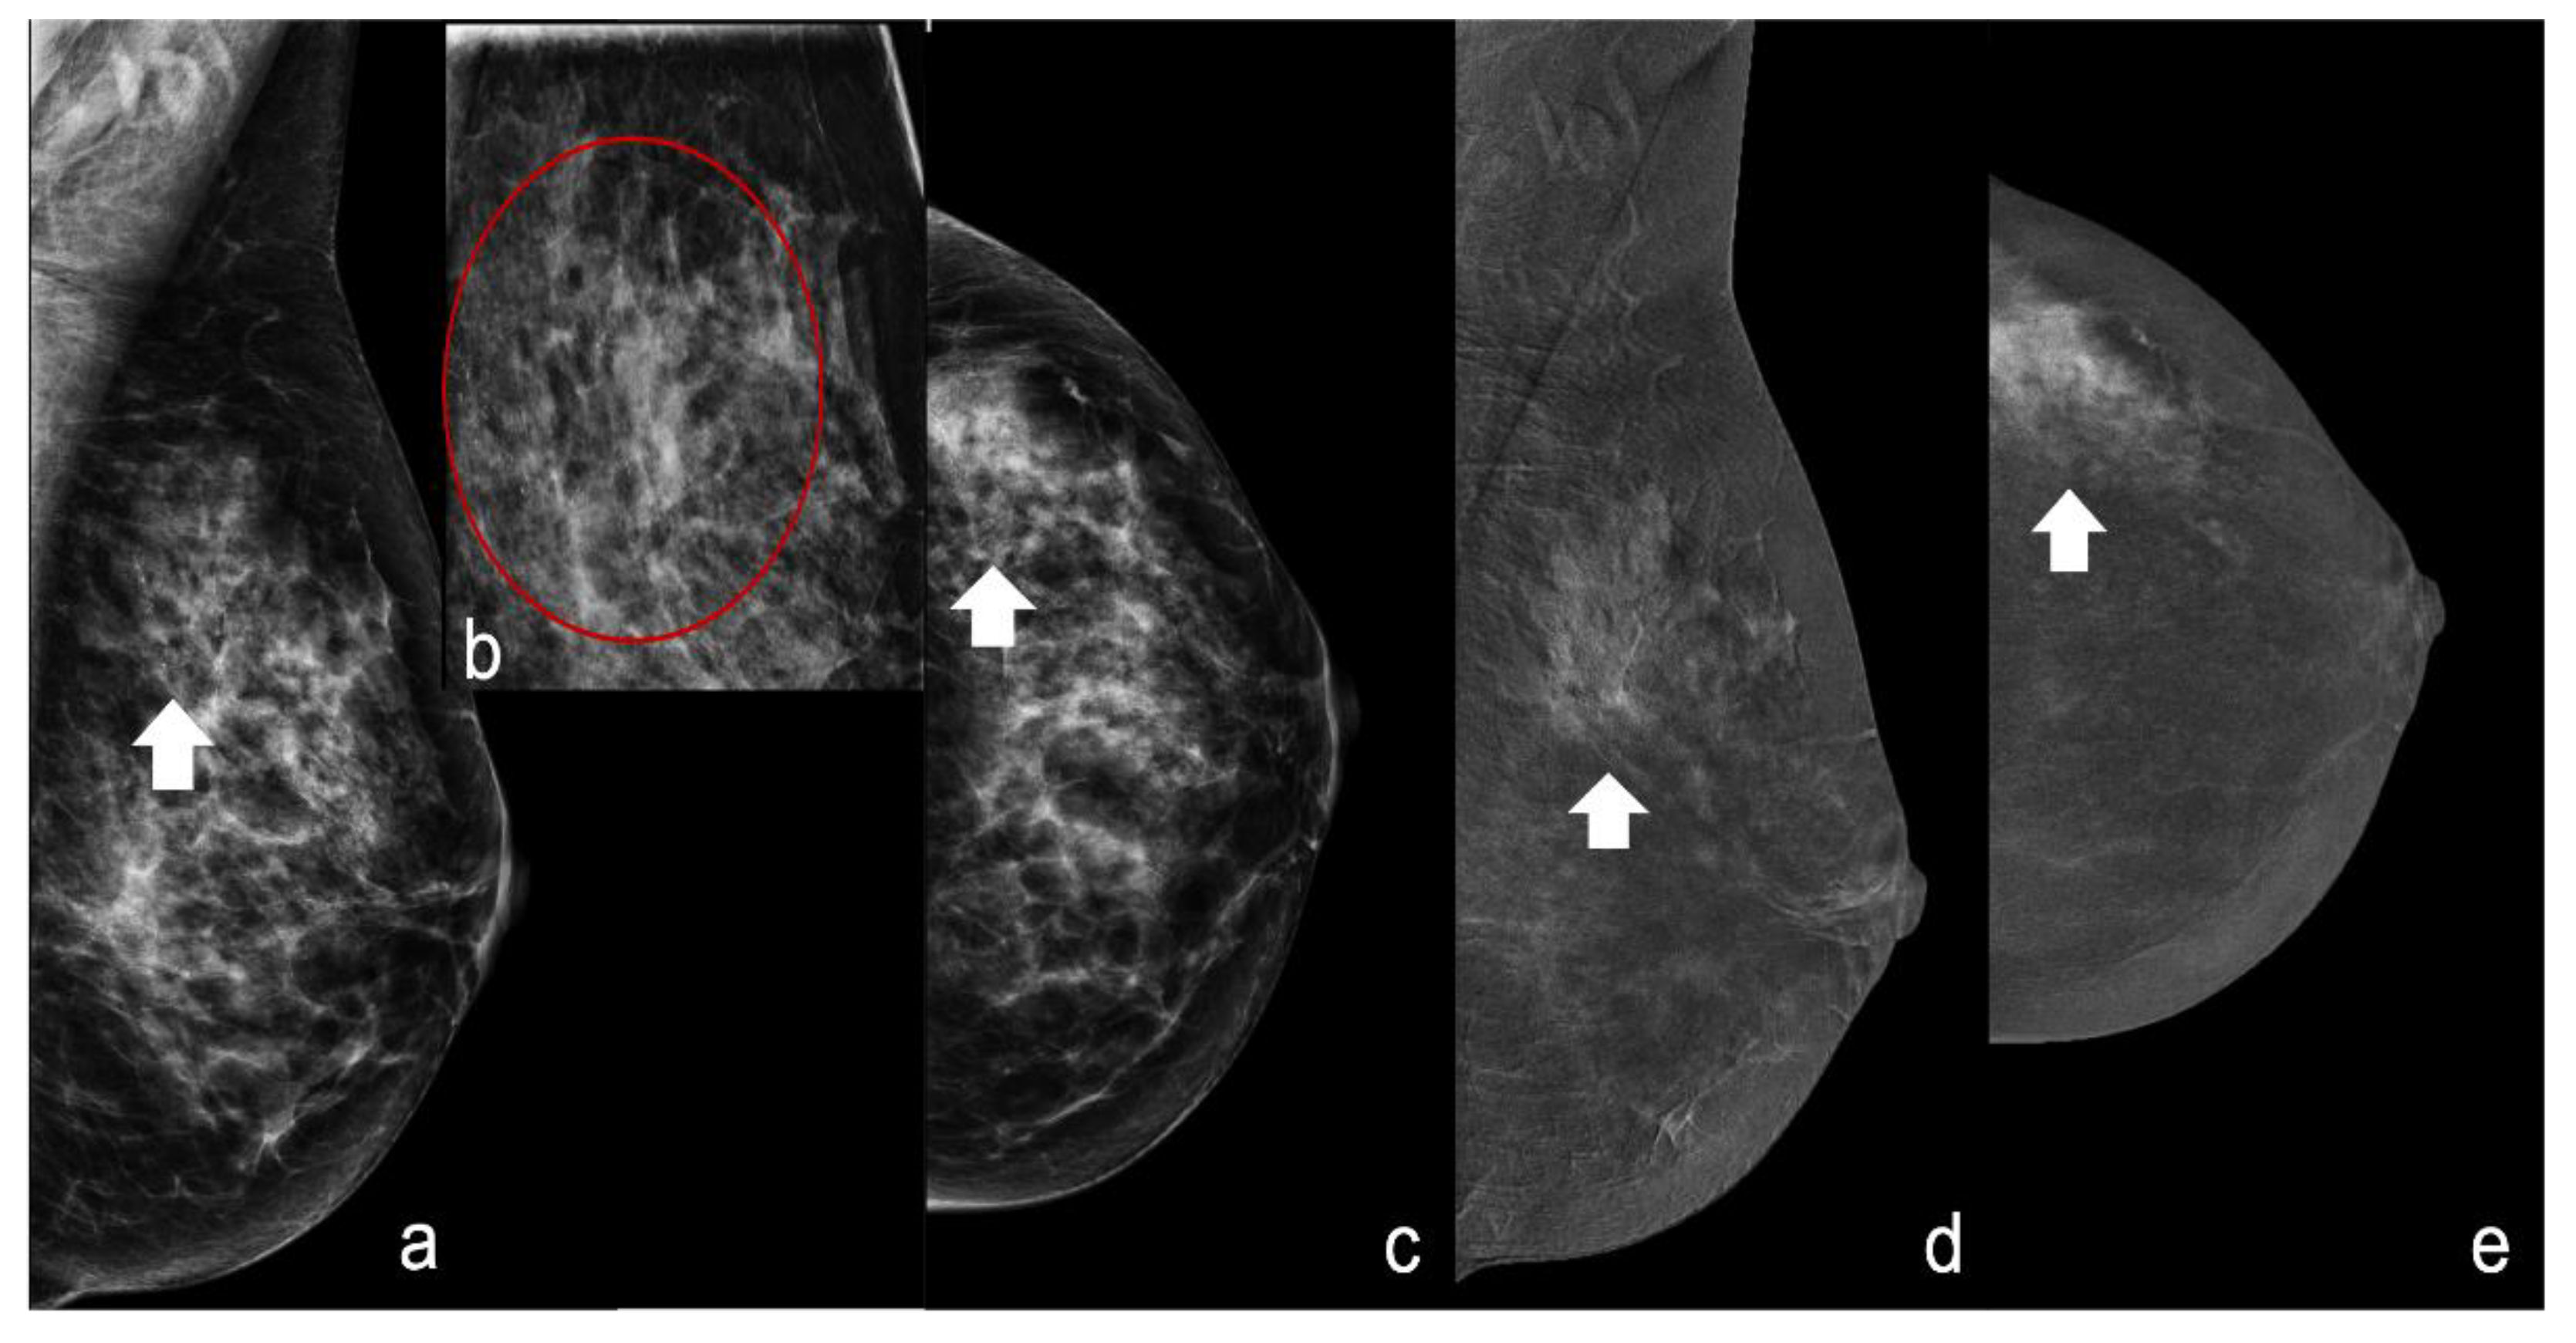

For the first analysis, we considered the unenhanced pattern (score 0) and minimally enhanced pattern (score 1) predictive of benignity and the moderately enhanced pattern (score 2) and markedly enhanced pattern (score 3) predictive of malignancy (Figure 1 and Figure 2).

Figure 2.

A 45-year-old patient with an extended segmental area of microcalcifications of the upper quadrants of the left breast. (a–c) Craniocaudal (CC) and mediolateral oblique (MLO) view and magnification of the upper quadrant of the left breast showing suspicious polymorphic microcalcifications (white arrowheads red circle). (d,e) CESM recombine images (CC and MLO view) showing a marked enhancement (score 3) at the site of suspicious microcalcifications (white arrowheads). Histology was high-grade invasive ductal carcinoma.